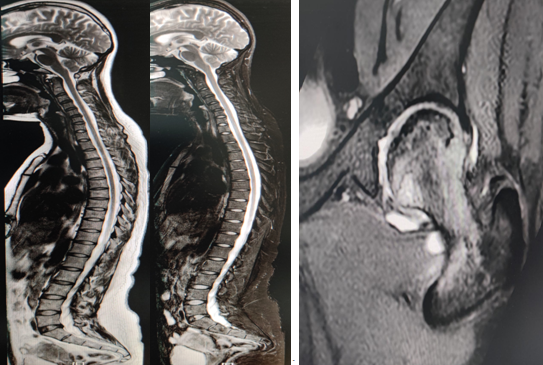

2.椎体肿瘤、外伤和感染、结核等;椎间盘病变、脊髓病变等。

3.全脊柱扫描、单侧髋关节扫描等。

全脊柱磁共振成像 单侧髋关节磁共振成像